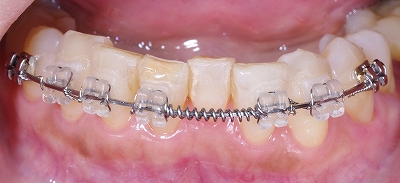

下顎歯列の凸凹の矯正治療

下顎の全体です。

前歯や小臼歯が歯列弓の中に納まりきれない状態です。

前歯の歯並びのバランスを考えるとスペースがどうしても足りません。

きれいに並びきれないので前歯一本をやむを得ず抜歯しました。

歯列全体にワイヤーをかけて矯正力をかけます。

少しずつゆっくりと歯列弓を拡大していきます。

小臼歯の並ぶスペースが確保できてきました。

矯正治療で歯並びが良くなる事は審美的な改善だけではなく歯周病や虫歯になるリスクを軽減します。

凸凹があるとプラーク(汚れ)が凹の部分に停滞しやすいのです。

歯ブラシが届きにくいのできれいに磨くのが困難です。

歯並びが整いました。

これなら歯ブラシが届きやすいのできれいに磨けます。